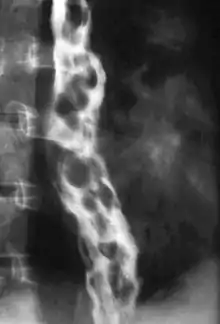

También pueden detectarse mediante radiografía aplicando una papilla de bario. En el medio de contraste se observan las lesiones como manchas negras, con típica conformación en collar de perlas o panal de abejas. Este método actualmente es poco localizado y a menudo no se ven siempre. La ecoendoscopia con Doppler se utiliza para obtener imágenes del flujo sanguíneo y su hemodinámica.[5]